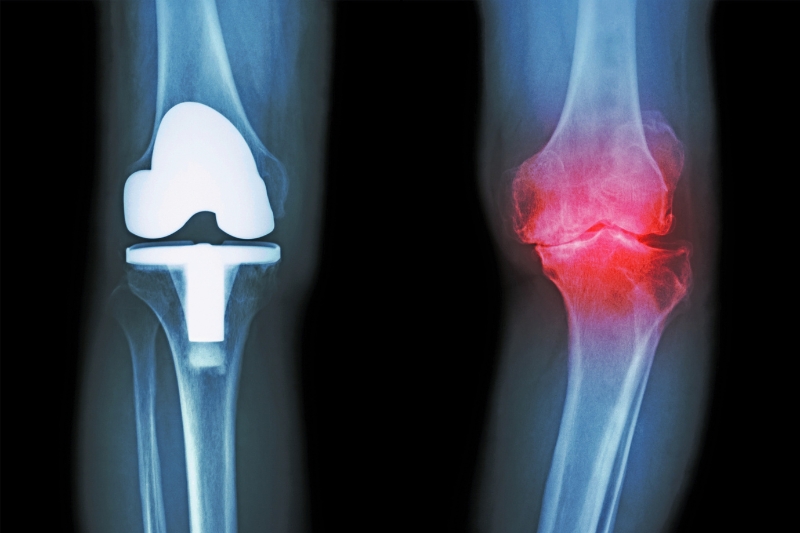

Térdprotézis műtét

A térdprotézis műtét olyan sebészeti eljárás, amely során a térdízület sérült vagy elhasználódott részeit mesterséges anyagból készült protézissel helyettesítjük, amely segíti a térd funkciójának helyreállítását, csökkenti a fájdalmat és javítja a mozgást.